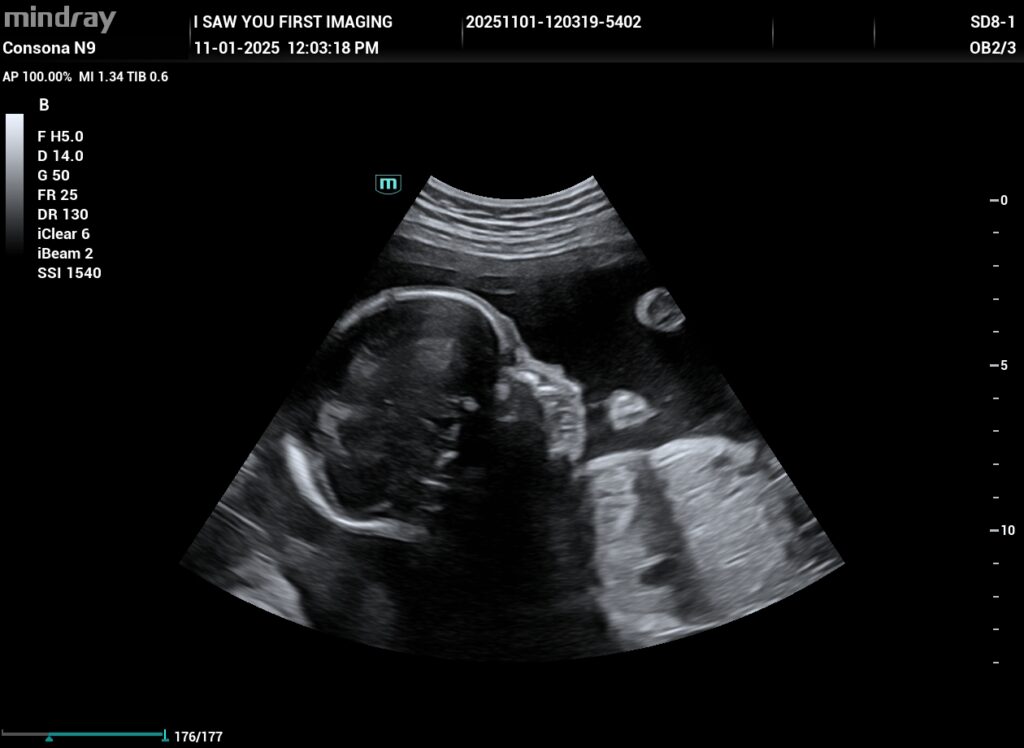

Gallery

Ready to Capture Your Baby's First Moments?

Memories are precious. We’re here to help you treasure them. Book your session today and step into a world of wonder. As a dedicated Pregnancy Care Centre in Moorestown, we’re committed to supporting you through every magical moment of your pregnancy journey. Your baby’s first photoshoot awaits!